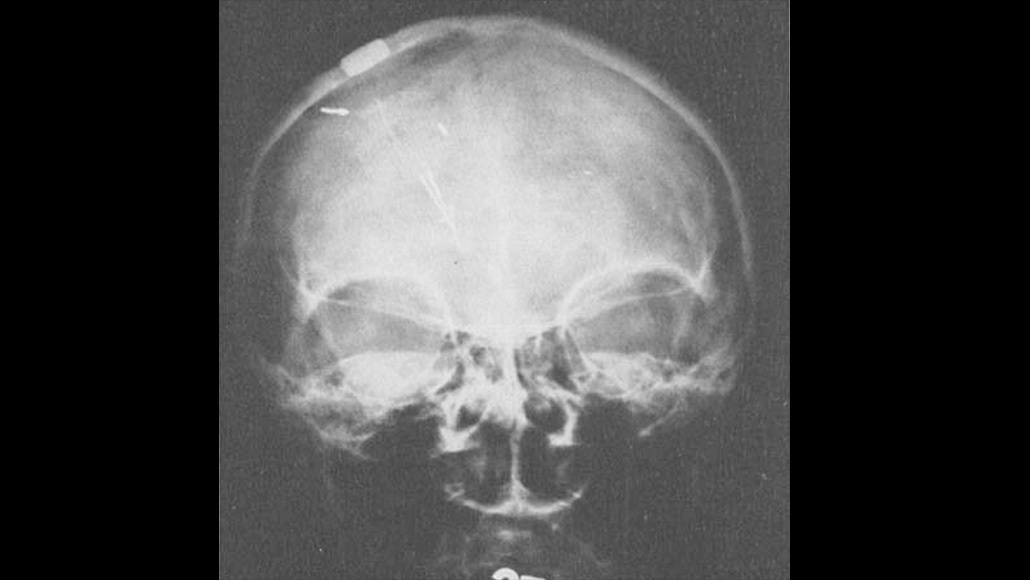

Electrodes for Parkinson’s J. L. Pool/J. Am. Geriatr. Soc 1954 By Science News January 1, 1948 at 7:13 pm - More than 2 years ago J. Lawrence Pool is the first to implant electrodes into a woman with Parkinson’s disease.